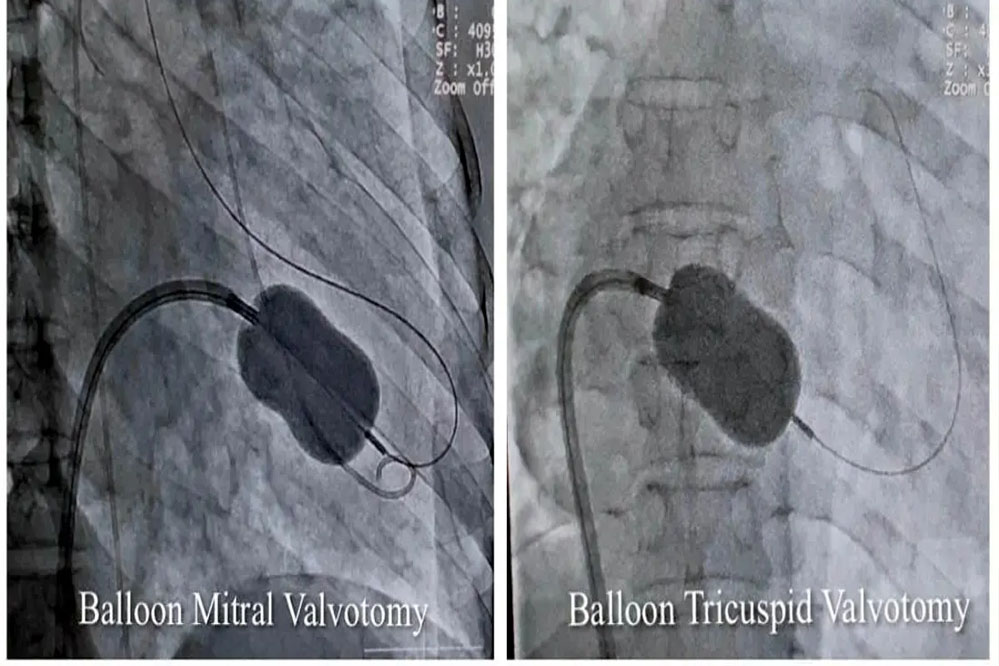

सुपर स्पेशलिटी अस्पताल के विशेषज्ञों ने बैलून तकनीक से मिट्रल व ट्राइकसपिड वॉल्व की सिकुड़न का बिना सर्जरी के इलाज किया

रयूमेटिक हृदय रोग से पीड़ित 40 वर्षीय महिला का मेडिकल कॉलेज के सुपर स्पेशलिटी अस्पताल के विशेषज्ञों ने बैलून तकनीक से मिट्रल व ट्राइकसपिड वॉल्व की सिकुड़न का बिना सर्जरी के इलाज किया। उपचार से मरीज को धड़कन की अनियमितता, बीपी, फेफड़े, पेट व अन्य जगह पर पानी भरने में भी आराम मिला है।

कार्डियोलॉजी विभाग के हृदय रोग विशेषज्ञ और ऐसोसिएट प्रोफेसर डॉ. शिशिर सोनी ने बताया कि मरीज को अत्यधिक गम्भीर अवस्था में सुपर स्पेशलिटी अस्पताल लाया गया था। इससे पहले उसे महाकोशल के कई अस्पतालों और नागपुर के हृदय रोग विशेषज्ञों को दिखाया जा चुका था, लेकिन इलाज नहीं हो सका। डॉ. सोनी ने बताया कि मरीज के मिट्रल और ट्राइकसपिड दोनों वॉल्व में स्टेनोसिस (सिकुडऩ) थी। इस बीमारी में मरीज को अत्यधिक सांस फूलने और पैरों में सूजन की समस्या होती है। इसके अलावा अन्य समस्याएं धडकऩों की अनियमितता, कम बीपी और फेफडें, पेट और अन्य जगहों में पानी भर जाने जैसी परेशानियां भी थीं। उन्होंने बैलून तकनीक से एक ही बार में परक्यूटेनियस मिट्रल और ट्राइकसपिड बैलून वाल्यूलोप्लास्टी सफलतापूर्वक की। इलाज के बाद महिला को पूर्णत: लाभ मिला है।

डॉ. शिशिर सोनी ने बताया कि एक ही मरीज में दोनों वॉल्व की सिकुड़न का परक्यूटेनियस मिट्रल और ट्राइकसपिड बैलून पाल्यूलोप्लास्टी से सफलतम उपचार दुनिया के कुछ ही कार्डियेक सेंटर में हुआ है। मध्यप्रदेश में यह उपचार पहली बार किया गया है।